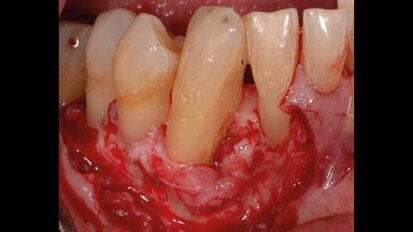

Biomateriali innovativi in implantologia: l’utilizzo di OsteoBiol Putty nel rialzo di seno transcrestale

Abstract Il rialzo di seno per via transcrestale rappresenta una procedura minimamente invasiva per aumentare il volume osseo nella regione posteriore del ...